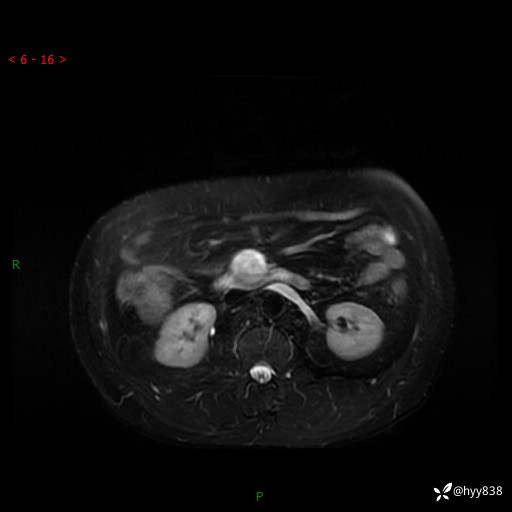

增强